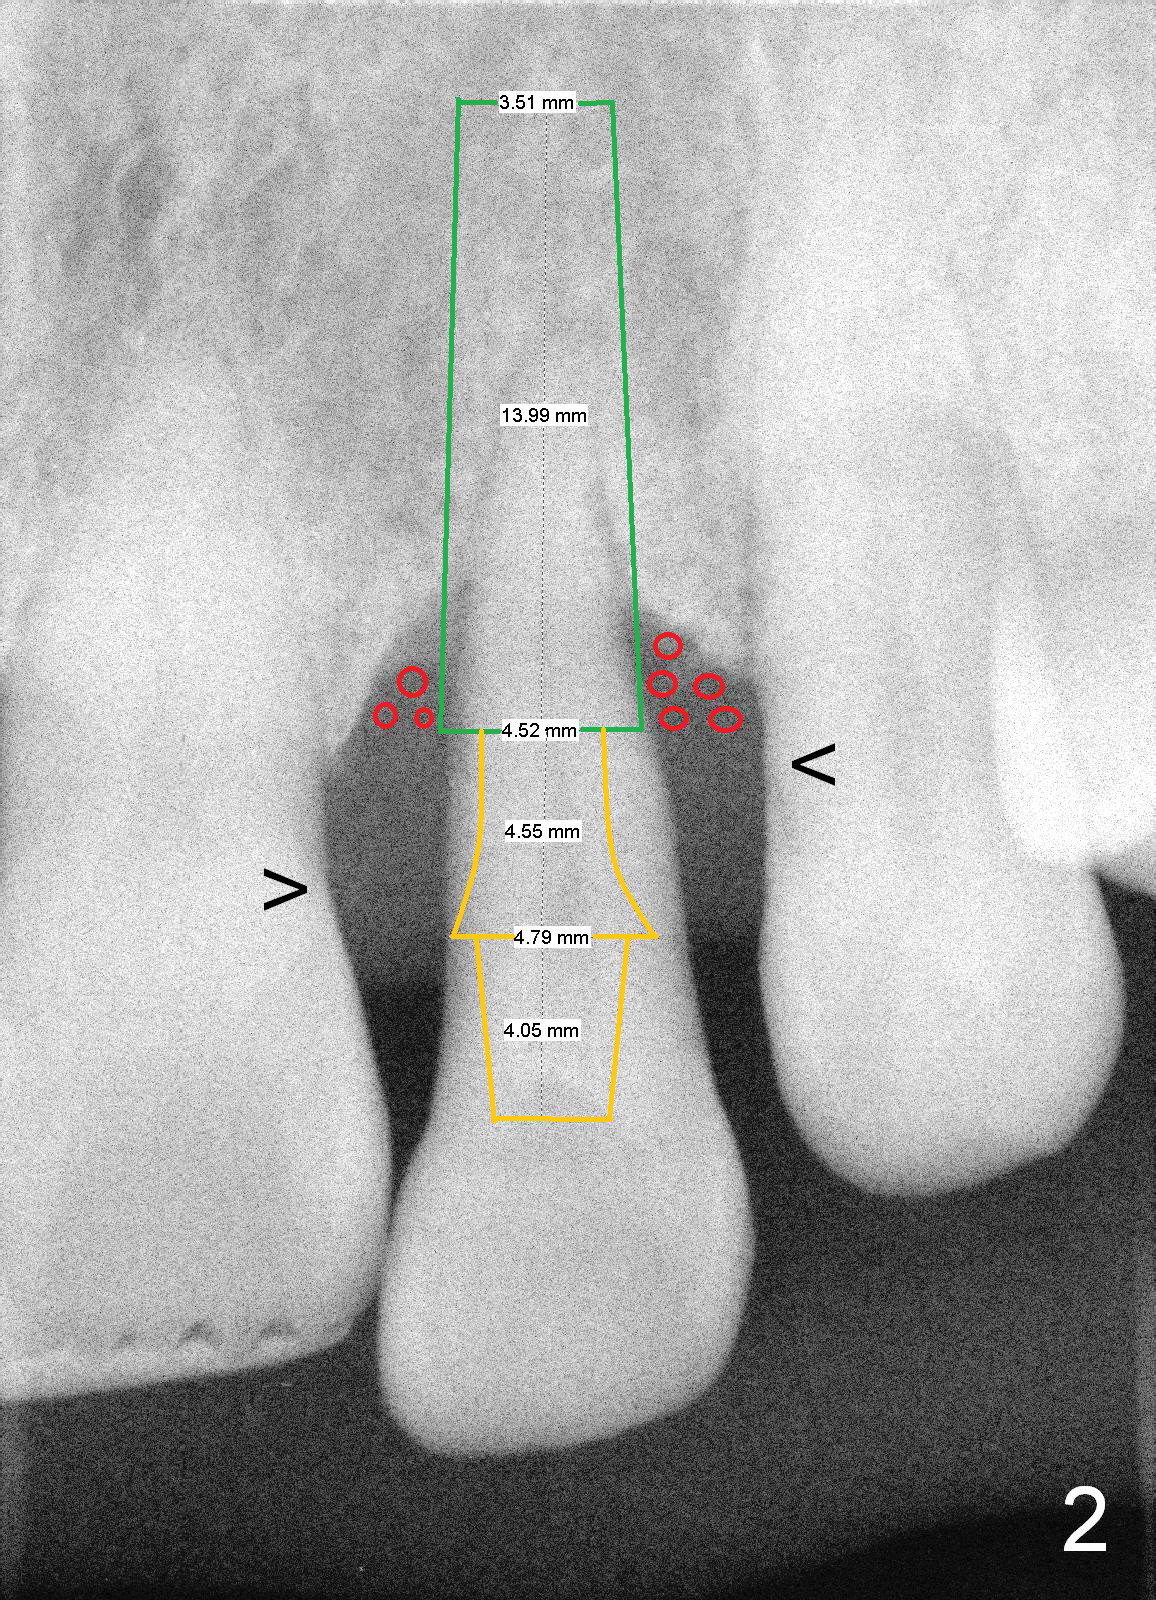

A 46-year-old lady has severe chronic periodontitis. The tooth #10 has drifted inferiorly and labially (Fig.1). One month and a half after #31 immediate implant, she wants to take care of #10. After extraction, measure the socket and tooth dimension. The implant (green box in Fig.2) diameter should be at least 2 mm smaller than the buccopalatal width of the socket. The platform of the implant should be 2-3 mm superior to the CEJ (cementoenamel junction (arrowheads)) of the neighboring teeth. The exposed implant threads will be covered by bone graft (red circles). Since the gingiva is thick (coronoapically), the abutment (gold color) cuff is expected to be 3-4 mm.